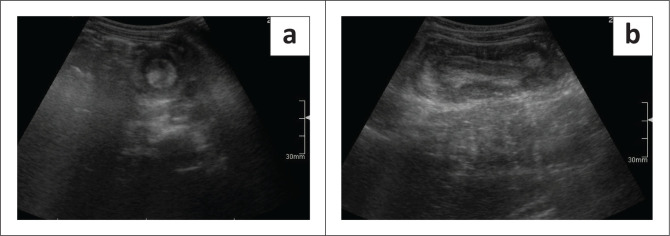

背景:肠套叠是儿童肠梗阻的常见原因,需要紧急处理以防止缺血。透视引导下的空气灌肠复位(FGAR)是无并发症病例的标准非手术治疗方法。目的:确定与小儿肠套叠FGAR结果相关的因素。方法:回顾性分析2016年11月至2022年12月在南非布隆方丹大学学术医院确诊的肠套叠患者110例。数据包括人口统计学、临床表现、实验室结果和影像学发现。结果:在110例患者中(中位年龄7个月,症状持续2天),37例主要手术治疗,73例进行FGAR尝试(31例成功,42例不成功,需要手术)。在79例手术病例中,24例采用手工复位而不切除。FGAR不成功与低龄(p = 0.0249)、脱水(p = 0.0299)、腹水(p = 0.0172)、超声显示外壁肠套叠直径增大(p = 0.0026)显著相关。结论:在这个南非队列中,不成功的FGAR与年轻、脱水、腹水和超声显示的较大的肠套叠大小有关。在资源有限的情况下,早期识别和常规超声使用对于提高非手术结果和减轻手术负担至关重要。贡献:本研究确定了低资源环境下FGAR失败的预测因素,为临床决策提供了信息,并解决了中低收入国家肠套叠管理文献中的空白。

Results: Among 110 cases (median age 7 months, symptom duration 2 days), 37 were primarily surgically managed, while 73 underwent FGAR attempts (31 successful, 42 unsuccessful, requiring surgery). Of the 79 surgical cases, 24 had manual reduction without resection. Unsuccessful FGAR was significantly associated with younger age (p = 0.0249), dehydration (p = 0.0299), ascites (p = 0.0172), and increased outer wall intussusception diameter on ultrasound (p = 0.0026).

Conclusion: In this South African cohort, unsuccessful FGAR was linked to younger age, dehydration, ascites, and larger intussusception size on ultrasound. Early recognition and routine ultrasound use are critical in resource-limited settings to enhance non-surgical outcomes and reduce surgical burden.